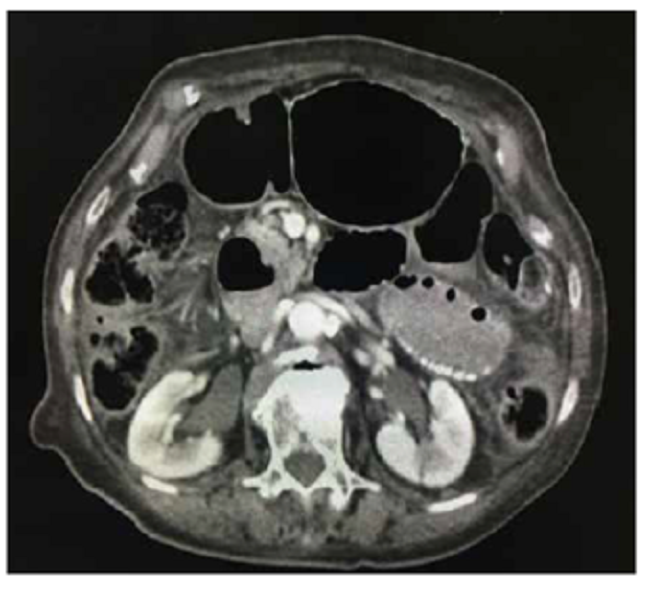

Por persistencia del cuadro clínico, se solicitó TC abdominal con contraste, en la que se apreció un íleo parcialmente obstructivo, hernia diafragmática derecha, dilatación esofágica indicativa de acalasia y derrame pleural y atelectasias en ambas bases pulmonares (figura 1 y 2.